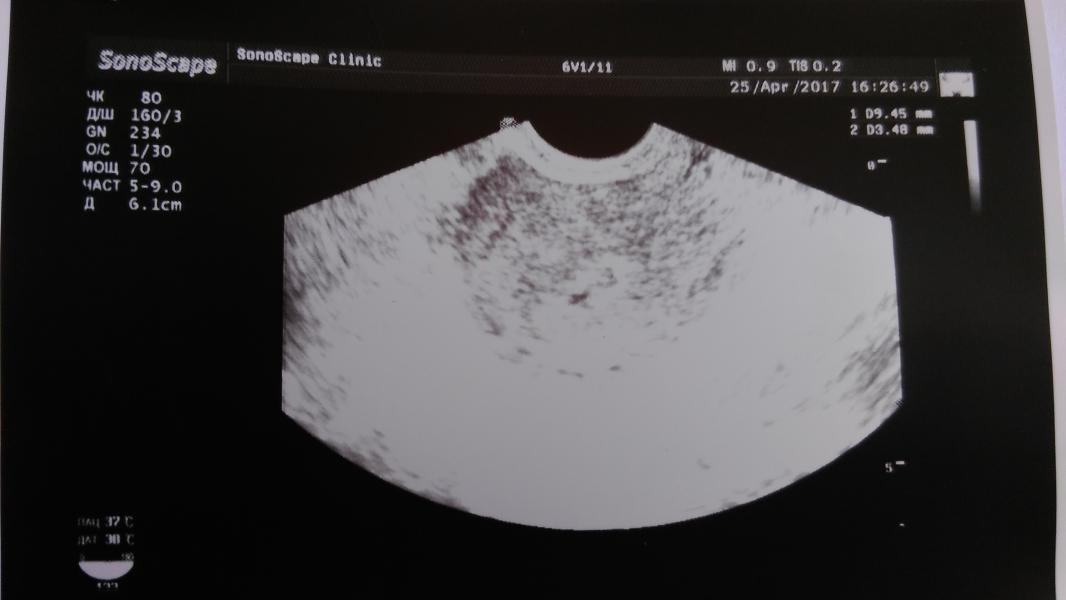

На фото УЗИ после чистки (((